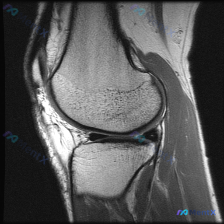

拿到这份病例和影像,先整理一下所有信息,再梳理思路: 一、核心临床问题 本次提出的核心疑问是:判断是否存在半月板异常 二、现有影像学发现(膝关节MRI T2序列冠状位单层面) 我先把所有客观发现整理出来: 1. 骨骼与关节软骨:股骨远端、胫骨近端骨皮质连续,无骨折;骨髓信号均匀,无明显水肿/硬化;关...

病例读片分享:临床怀疑半月板异常,单层面MRI怎么看? 今天整理了一份膝关节MRI读片病例,核心问题是临床怀疑半月板异常,但我们拿到的只有一份单冠状位的脂肪抑制序列图像,分享一下我的分析思路。 一、影像基本信息 这是一张膝关节MRI的冠状位脂肪抑制(PD-FS或T2-FS)扫描图像,这类序列对水/液...

看到一份膝关节MRI的影像资料,问题是观察半月板异常,整理一下完整分析思路分享给大家。 病例基本影像信息 这是一份膝关节冠状位T1加权MRI的单影像分析,核心异常聚焦在半月板: 1. 骨骼结构:股骨远端、胫骨近端骨质信号均匀,无骨髓水肿、骨质破坏,皮质连续完整 2. 关节软骨:关节面软骨形态规整,无...

看到一个有意思的影像讨论病例,整理一下资料和思路分享给大家。 病例背景 提问:单张膝关节冠状位MRI图像,问题是图像中可见的异常是什么,提示半月板异常。 影像初步分析 先确认这张影像的基本信息:这是膝关节冠状位MRI,对比良好,骨髓信号正常,可以看到股骨远端、胫骨近端、内外侧关节间隙、半月板和侧副韧...